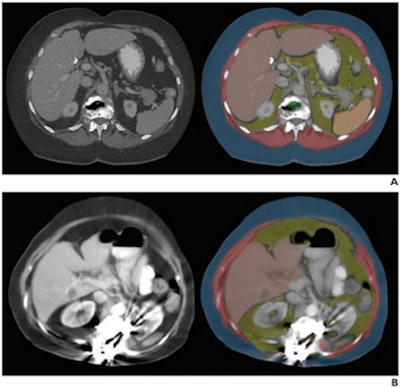

Axial images at L1 level, without (left) and with (right) segmentation overlay. Red indicates skeletal muscle, green indicates trabecular bone, yellow indicates visceral fat, and blue indicates subcutaneous fat. Segmented regions also include liver (beige) and spleen (orange), which were not evaluated as part of present analysis. (A) 78-year-old woman who underwent abdominopelvic CT at an outside institution. Bone tool returned L1 vertebral body bone attenuation of -146 Hounsfield units (HU), outside of reference range. Thus, the tool was deemed technical failure for bone tool. Failure was attributed to volume averaging of vacuum phenomenon within slice. (B) 64-year-old woman who underwent abdominopelvic CT at an outside institution. Bone tool returned vertebral body bone attenuation of -10,000 HU (default value for segmentation failure detected by tool), outside of reference range. Thus, the tool was deemed technical failure for bone tool. Failure was attributed to the presence of spinal fusion hardware. Images and caption courtesy of the American Journal of Roentgenology.

Axial images at L1 level, without (left) and with (right) segmentation overlay. Red indicates skeletal muscle, green indicates trabecular bone, yellow indicates visceral fat, and blue indicates subcutaneous fat. Segmented regions also include liver (beige) and spleen (orange), which were not evaluated as part of present analysis. (A) 78-year-old woman who underwent abdominopelvic CT at an outside institution. Bone tool returned L1 vertebral body bone attenuation of -146 Hounsfield units (HU), outside of reference range. Thus, the tool was deemed technical failure for bone tool. Failure was attributed to volume averaging of vacuum phenomenon within slice. (B) 64-year-old woman who underwent abdominopelvic CT at an outside institution. Bone tool returned vertebral body bone attenuation of -10,000 HU (default value for segmentation failure detected by tool), outside of reference range. Thus, the tool was deemed technical failure for bone tool. Failure was attributed to the presence of spinal fusion hardware. Images and caption courtesy of the American Journal of Roentgenology.The group reported that the three automated AI tools for measuring body composition were technically adequate in 97.7% of the CT exams. The failure rate was 2.3%, and these failures were primarily (88%) due to an image processing error caused by incorrect DICOM header voxel dimension information (i.e., an anisometry error).